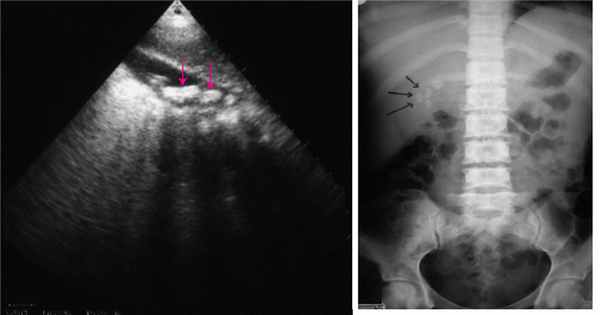

Анатомическое расположение и малый размер ампулярных опухолей определяют сложность их диагностики. Заподозрить заболевание позволяют такие признаки, как дилатация общего желчного протока и/или главного панкреатического протока [21]. Уровень онкомаркера CA19-9 не является специфичным признаком и, по данным ряда исследований, повышен лишь у 63% пациентов с аденокарциномой БСДК [12].

Для диагностики и стадирования ампулярной опухоли используются дуоденоскопия, трансабдоминальное ультразвуковое сканирование брюшной полости, мультиспиральная компьютерная томография (МСКТ) с внутривенным контрастированием, магнитно-резонансная томография (МРТ), позитронно-эмиссионная томография (ПЭТ) и эндоскопическая ультрасонография.

Необходимо отметить, что размер опухоли не является критерием малигнизации. В исследованиях были проанализированы морфологические характеристики новообразований БСДК у 450 пациентов. Средний размер аденокарциномы составил 2,0 см, аденомы – 2,9 см [1, 12, 22]. Тем не менее исследователи предположили, что размер опухоли имеет значение для прогнозирования злокачественности. Согласно результатам исследования, размер более 3,0 см подтвержден в 28% случаев аденокарцином и только в 12% случаев аденомы [14]. Показатели частоты обнаружения опухолей БСДК при ультразвуковом исследовании брюшной полости варьируются от 12 до 27% [22, 23].